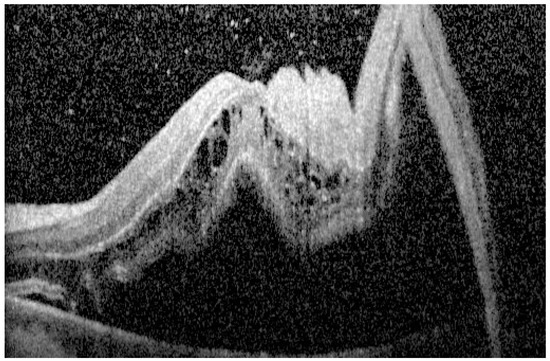

2.1.6. Outer Retinal Undulations

| Outer retinal undulations (ORUs) | Directional changes in the outer retinal contour | More common in subacute detachments, may serve as a marker for detachment duration and potential for reversible damage [17,33] |